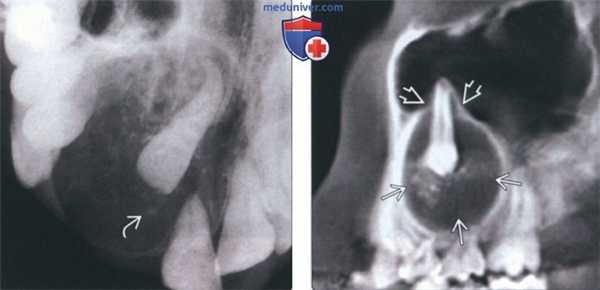

(Слева) На окклюзинной рентгенограмме передних отделов верхней челюсти справа в АОО визуализируется импактный боковой резец. Обратите внимание на едва различимый кальцинат в рентгенонегативном матриксе опухоли.

(Справа) На сагиттальной КЛКТ определяется АОО, связанная с премоляром верхней челюсти. Кортикальная пластинка опухоли крепится к корню зуба в средней третий. Обратите внимание на кальцинаты в центре и периферическое просветление - частая картина АОО.